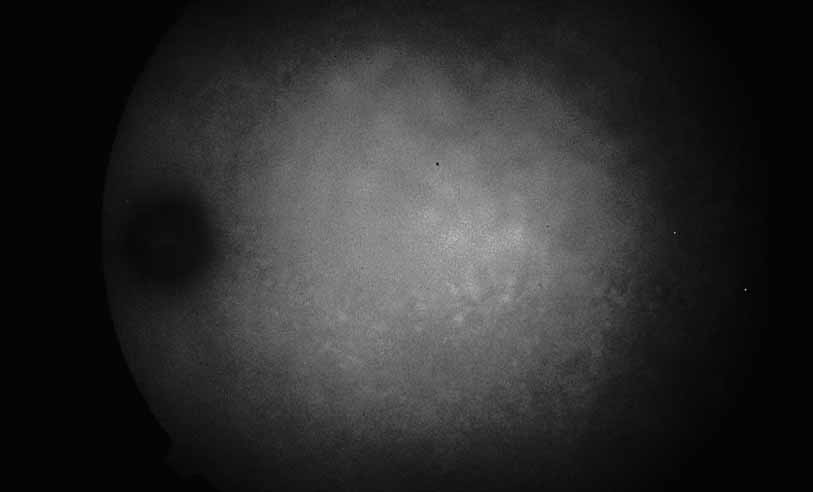

A third instance in which fluorescein angiography concentrating on the optic nerve may be helpful is in eyes with vascular engorgement of the optic nerve, especially with media opacities. Fluorescein angiography may help the clinician distinguish abnormally leaking capillaries from neovascularization. In acute multifocal hemorrhagic retinal vasculitis, optic nerve involvement is common in the early stages of the disease, 47 with optic nerve disc neovascularization seen later (see Figs. 10, 11, 12, and 13). Another fluorescein angiographic clue to the distinction between optic disc vessel engorgement and true neovascularization is the presence of associated large zones of retinal capillary nonperfusion such as those seen in sarcoidosis (see Figs. 14 and 15),34–40 acute multifocal hemorrhagic retinal vasculitis (see Figs. 10 and 11),47 or Eale disease (see Figs. 16 and 17).48–52

Fig. 10 Acute multifocal hemorrhagic retinal vasculitis. A middle-aged man presented with the picture of multiple branch vein obstructions and low-grade intraocular inflammation.

Fig. 11 Acute multifocal hemorrhagic retinal vasculitis. Fluorescein angiogram confirms the presence of associated retinal capillary non-perfusion without neovascularization at the onset of the disease.

Fig. 12 Acute multifocal hemorrhagic retinal vasculitis. The patient later developed disk neovascularization with vitreous hemorrhage. Note the areas of neovascular leakage from the optic nerve.

Fig. 13 Acute multifocal hemorrhagic retinal vasculitis. The patient underwent scatter laser photocoagulation to the zones of retinal capillary nonperfusion, which resulted in regression of the neovascularization.